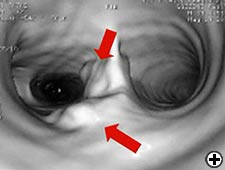

Cardiac function is assessed based on a physical examination, electrocardiography, and transthoracic echocardiography in all patients. Radiological work-up includes standard chest X-ray, total body CT-scan, bone scintigraphy and PET scan, where indicated. All patients should be submitted to rigid bronchoscopy (Figure 3) and sometimes to virtual bronchoscopy (Figure 4) to precisely assess the extent of invasion and the required resection. Mediastinoscopy (in case of malignant tumors), performed at the time of planned resection, may be useful to discover potentially involved lymph nodes, to evaluate the mediastinal and extraluminal spread of the neoplasm and to dissect the pretracheal plane, enhancing the mobility of upper trachea and reducing the risk of recurrent laryngeal nerve injury.